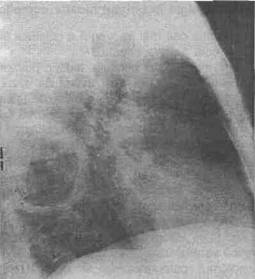

9. Tn chistui hidatic complicat examenul radiologic este caracteristic:

b. Tn eel evacuat: cavitatea intraparenchima-toasa bine delimitata cu semnul membranei ondu-late pe fundul lojei chistice (fig. 3, 4, 5).

Fig. 5 - Radiografie profil drept, imagine tipicS de chist hidatic evacuat cu mernbrana Tncarcerata pe fundul cavitatii - situata In lobul superior drept.